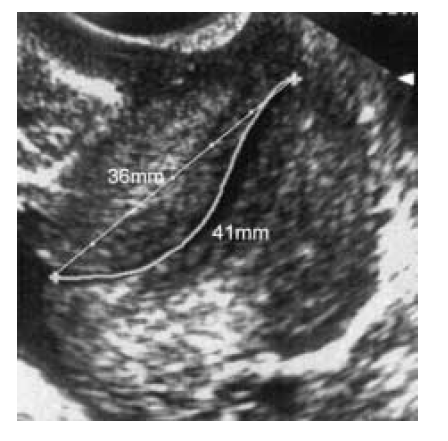

6. The sonolucent endocervical mucosa should be identified as a guide to the true position of the internal os. The callipers should be placed to measure the linear distance between the triangular area of echodensity at the external os and the V-shaped notch at the internal os.